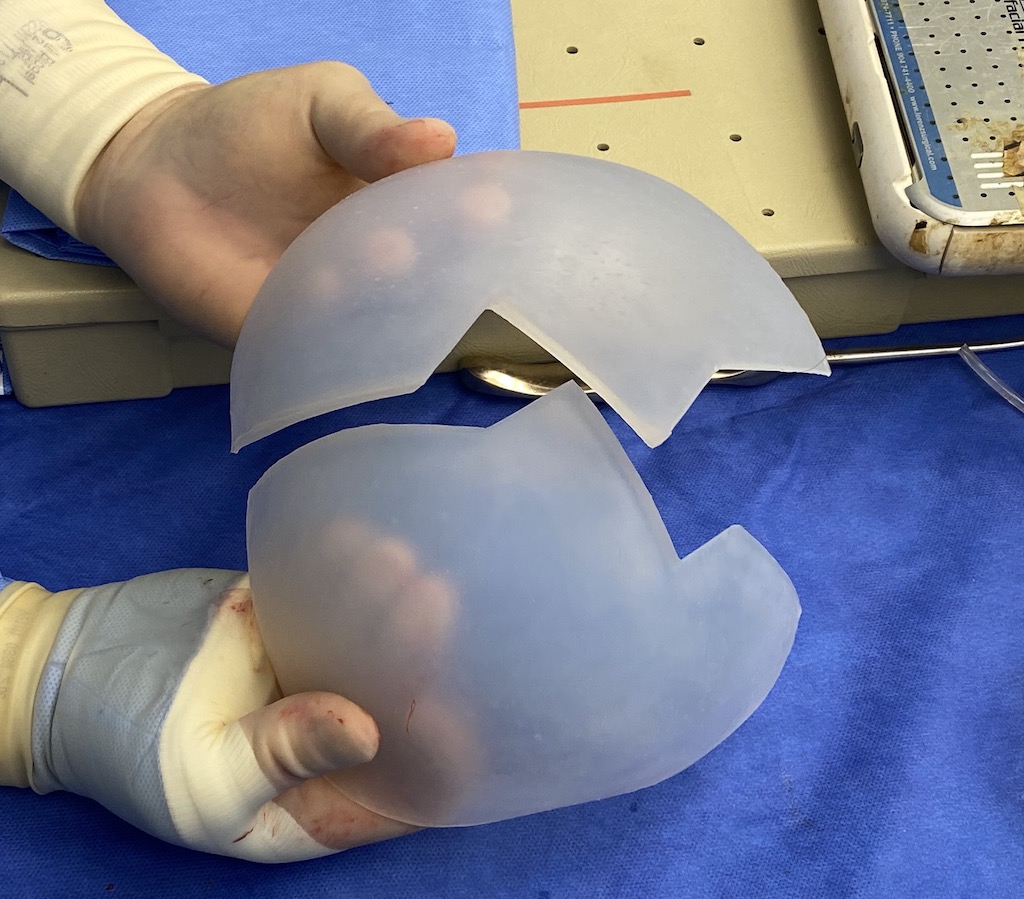

Desire for major head reshaping with a taler and wider head shape.

Placement of large two piece custom skull implant through a sagittal scalp incision.

Desire for major head reshaping with a taler and wider head shape.

Placement of large two piece custom skull implant through a sagittal scalp incision.